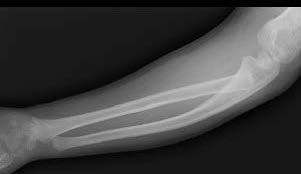

Case 2. Chronic Monteggia with deformed radial head